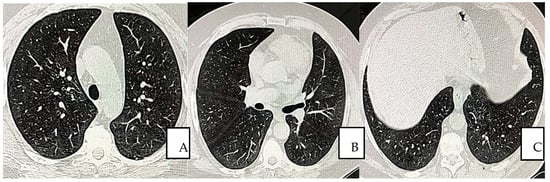

The overall condition improved within 10 days after the first transfusion. The HRCT values became completely negative at day 60 after the 12th transfusion (Figure 3A–C).

Figure 3.

(A–C) Pulmonary non-contrast enhanced chest CT scan obtained on day 60 from symptom onset (16 February 2021), shows continued and completed resolution without residuals. Parenchymal, mediastinum, and peripheral (A,B), lower lobe I opacities and bands are not observed (A,B).